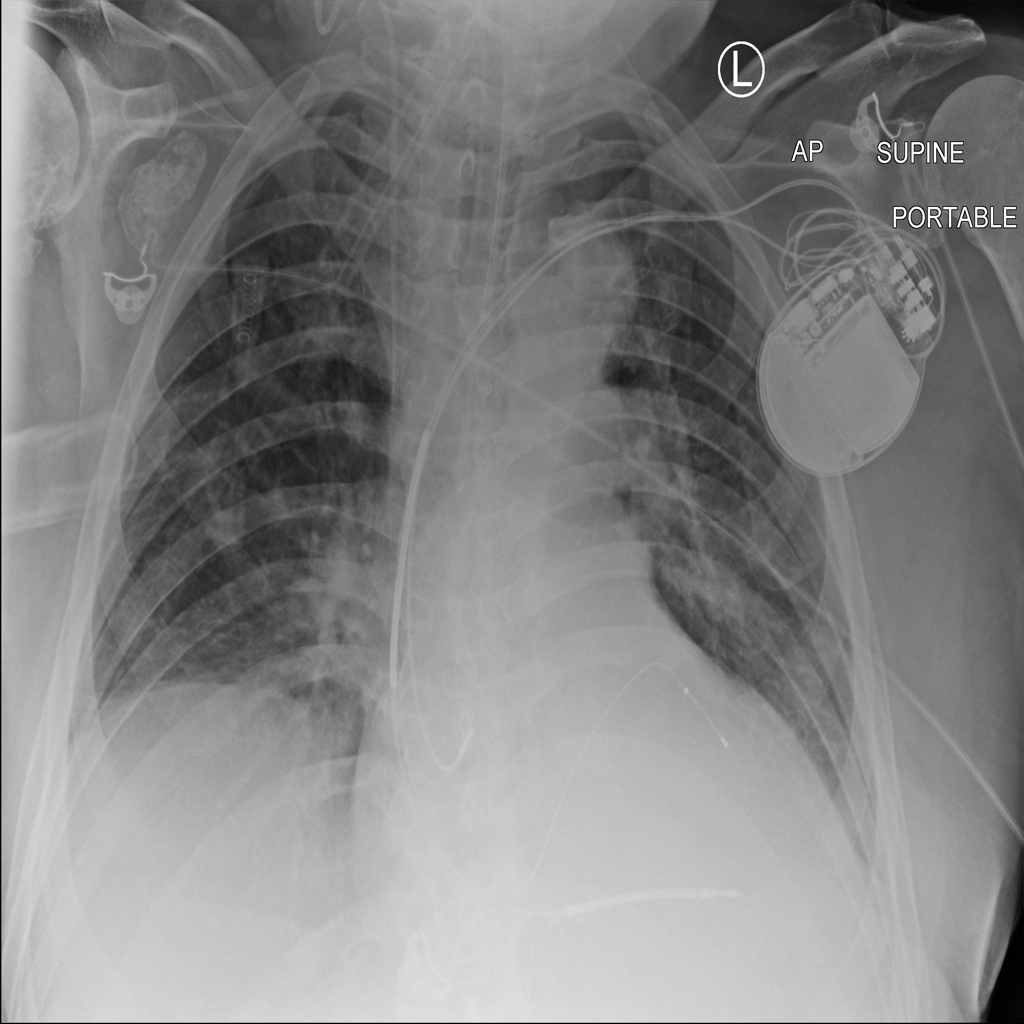

PAT-F3E7 · IMG-000Cardiomegaly

PAT-F3E7 · IMG-000

PA